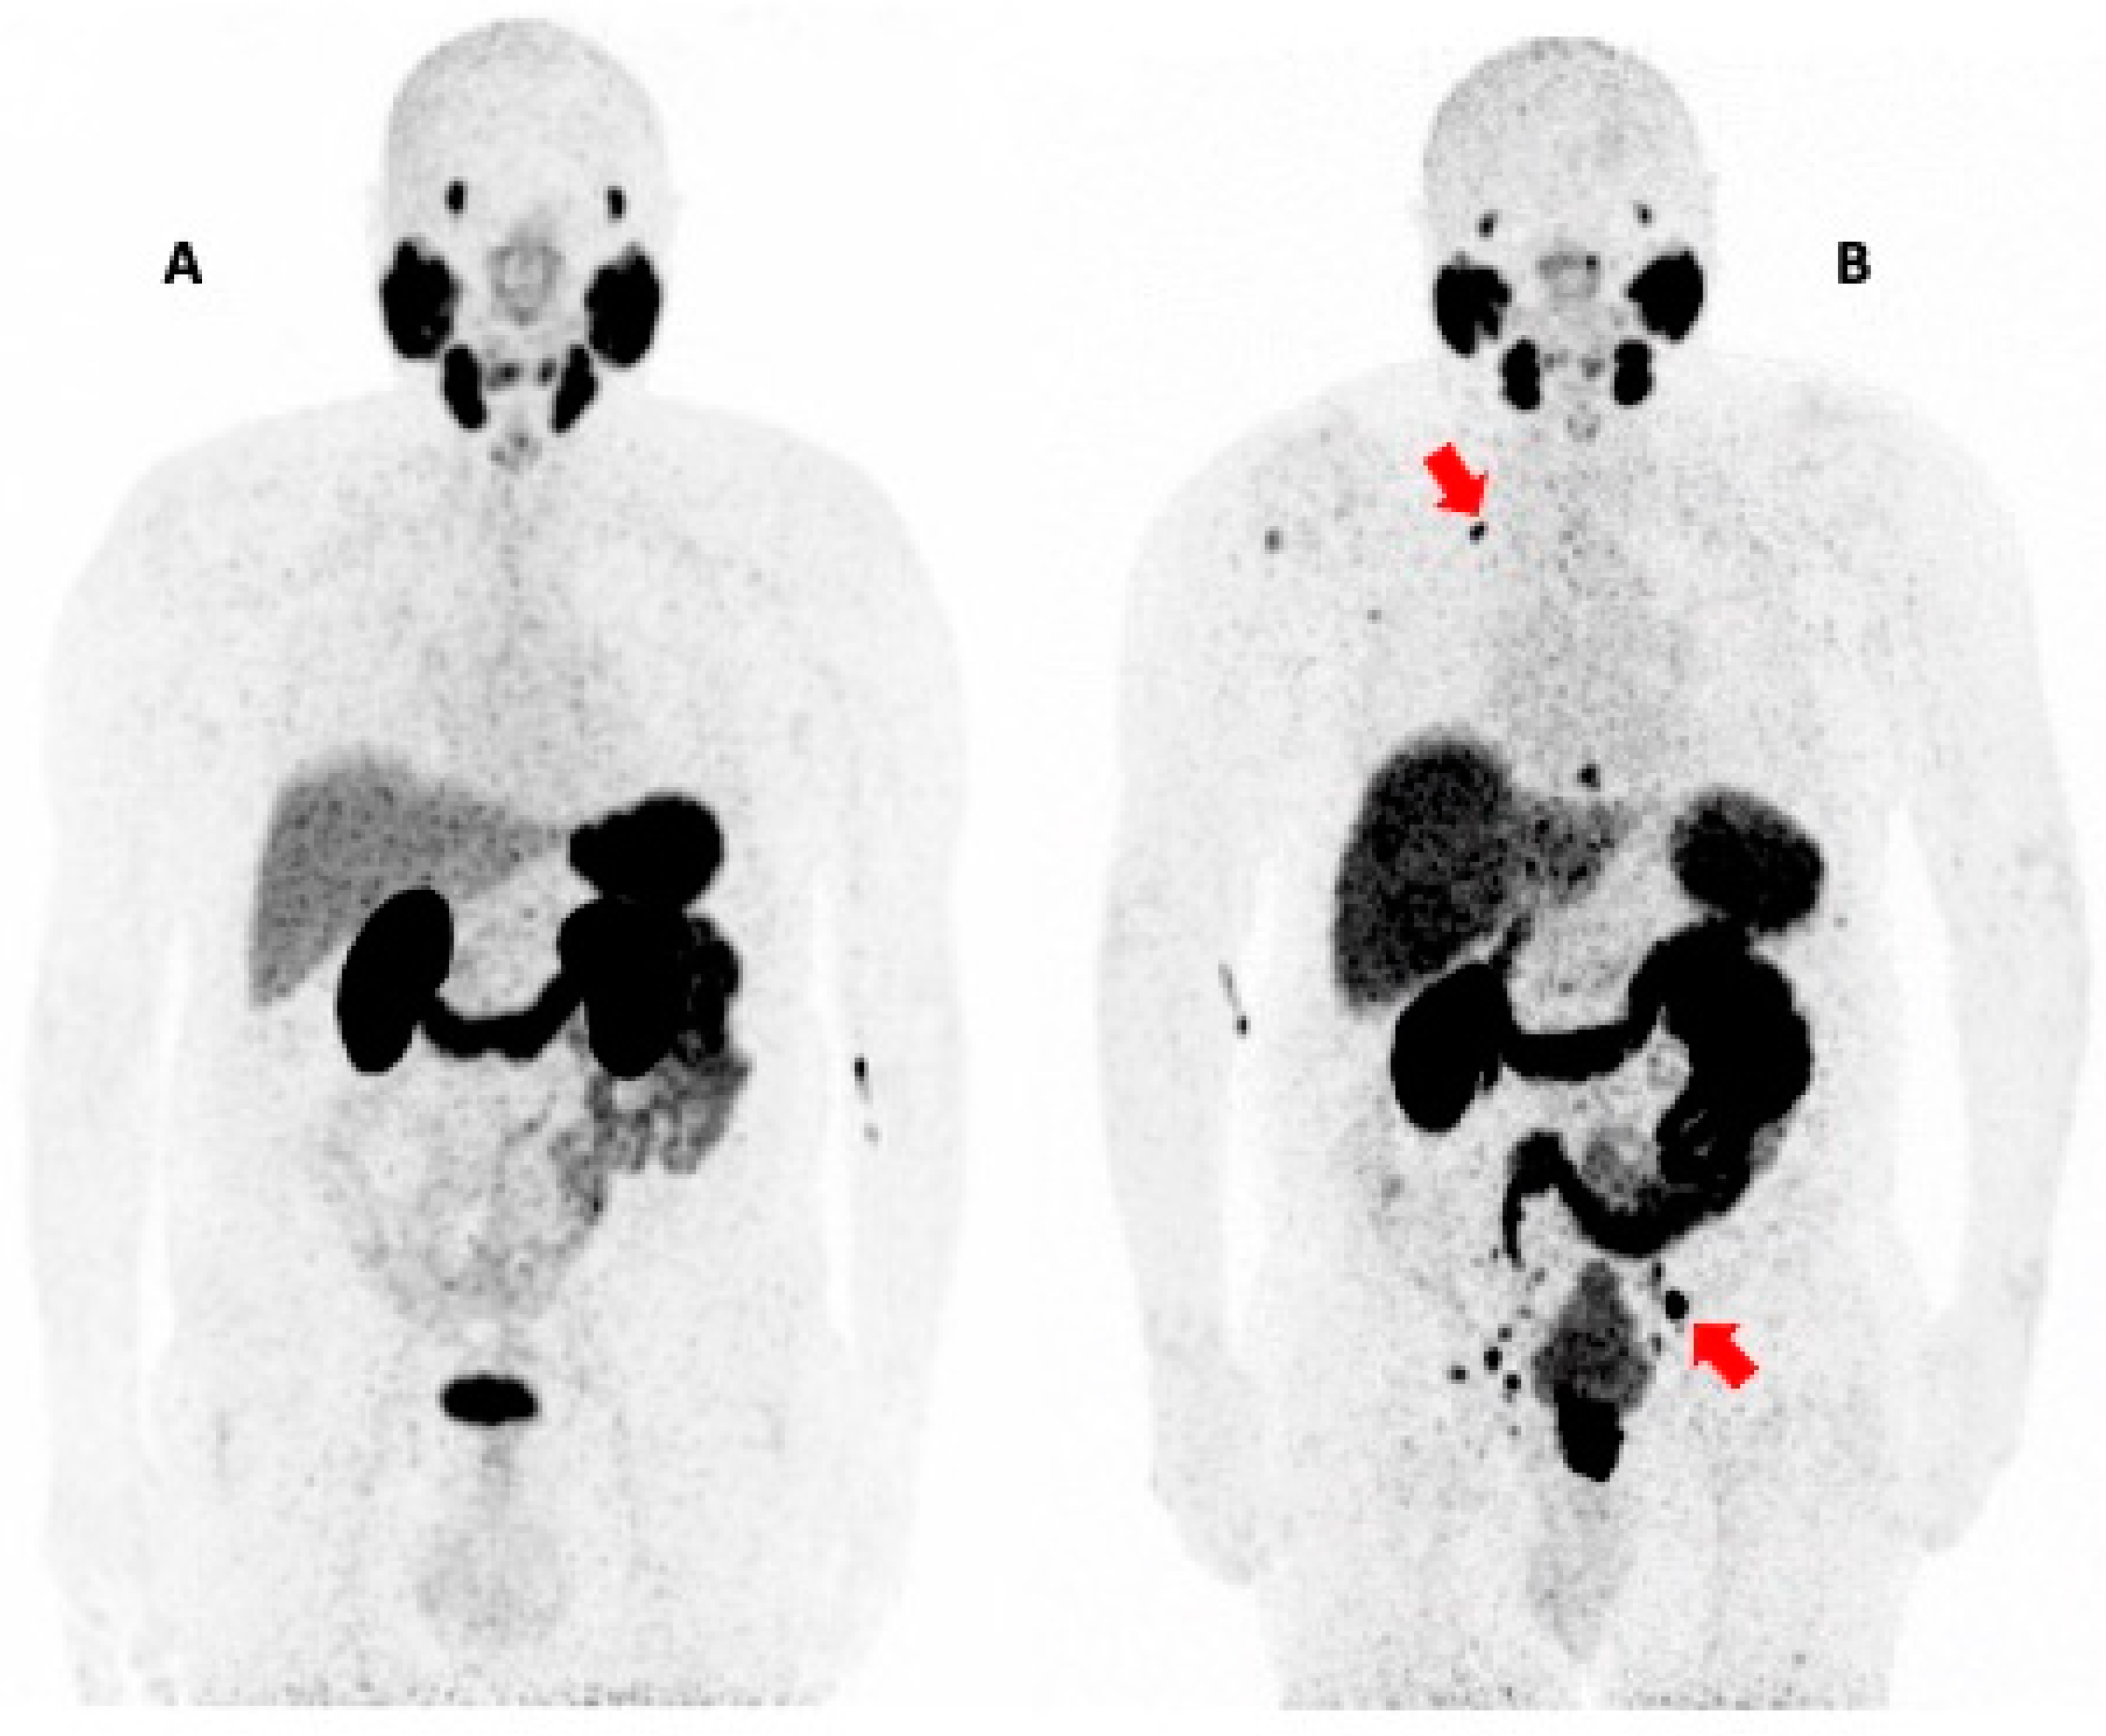

- Evbuomwan, O.; Endres, W.; Tebeila, T.; Engelbrecht, G. Atypical Presentation of Metastatic Castrate-Resistant Prostate Cancer in a Middle Aged African Male with Good Response to Radioligand Therapy. Mirt 2024, 33, 57–62. [Google Scholar] [CrossRef]